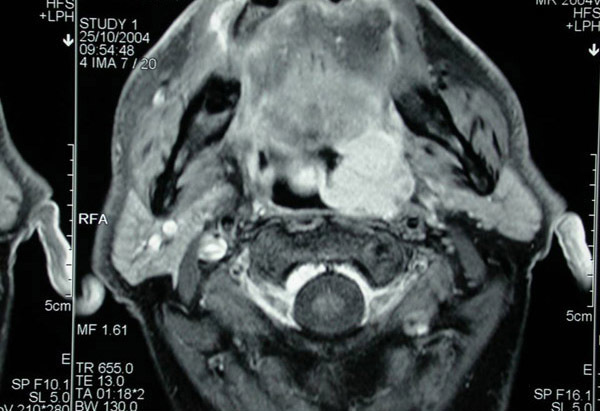

Coupe IRM axiale montrant une tumeur de la paroi latérale gauche de l’oropharynx. Le contraste tissulaire est bien supérieur.